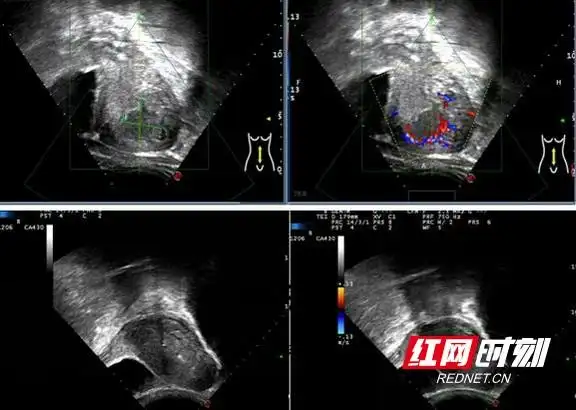

岳阳市妇幼保健院海扶刀成功治疗胎盘植入